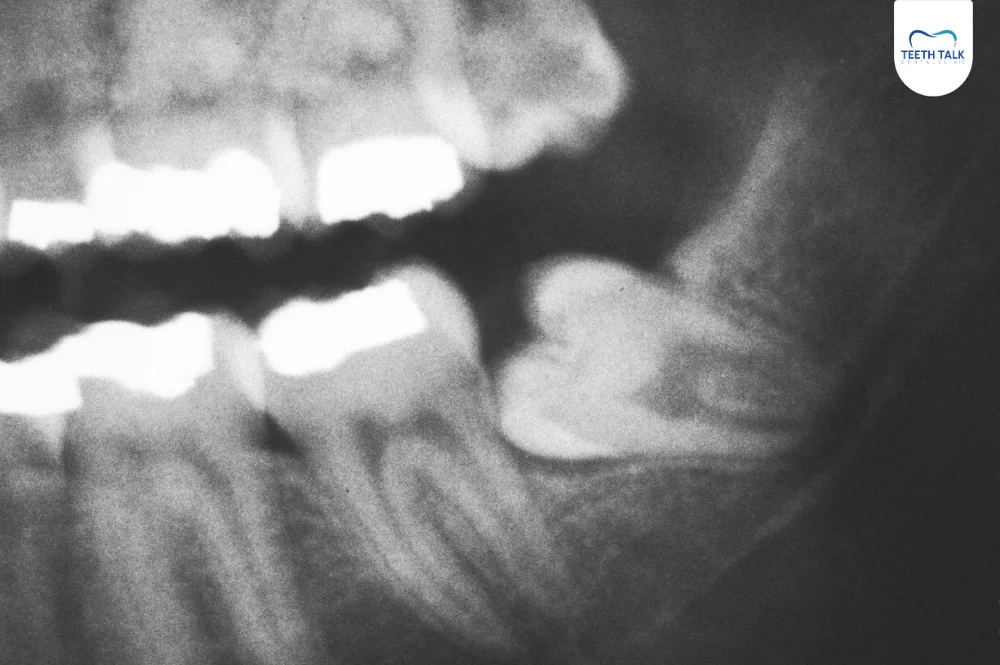

1. ฟันคุด

ฟันคุด (Impacted Tooth) คือสาเหตุยอดฮิตของอาการปวดฟันกรามรุนแรง โดยเฉพาะฟันคุดซี่ล่างที่อยู่ใกล้เส้นประสาทและข้อต่อขากรรไกร เมื่อฟันคุดพยายามดันขึ้นมา หรือเกิดการอักเสบติดเชื้อ แรงดันและความปวดจึงลามไปถึงหูได้ง่าย หากปล่อยไว้นานอาจต้องรับการถอนฟันคุดที่ซับซ้อนขึ้น

- วินิจฉัยแม่นยำด้วยเทคโนโลยี : เรามีเครื่อง X-ray และ CT Scan 3 มิติ ที่ช่วยให้เห็นต้นตอของปัญหาชัดเจน ว่ามาจากฟันคุด รากฟัน หรือข้อต่อขากรรไกร